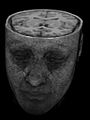

-

3D-Rekonstruktion (Volumenrendering) eines MRT-Datensatzes